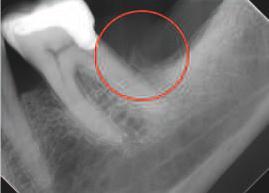

Figurile: 1. Rx bite-wing prezentată cu detectări AI clinice și măsurători ale nivelului osos. Detectările cariei (fuchsia) indică adâncimea cariei în diverse structuri ale dinților. În acest exemplu sunt evidențiate și tartrul (verde) alături de o margine evidentă (mov). 2. Rx periapicală prezentată în cadrul unei interfețe AI radiologice de la scaunul stomatologic. Clinicienii pot activa segmentările porțiunilor dentare, care furnizează o hartă colorată a structurilor dinților pentru a ajuta la prezentarea cazului și la educarea pacienților.